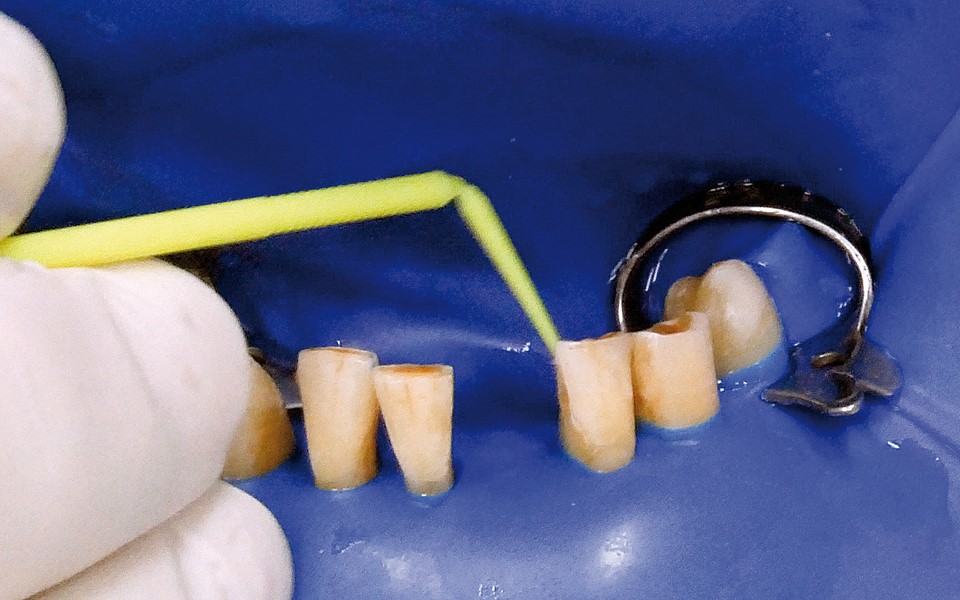

One of the more popular methods of stabilising loose teeth is to splint them. This method, aiding other methods of treatment, is generally used. One of the most modern materials used in dentistry for splinting teeth, is polyamide tape. In the case described the authors show how to simplify the whole procedure and limit the risk of making a mistake, particularly in the situation of total loss of one tooth. This was achieved thanks to the use of an index made out of transparent silicone.

Jedną z popularniejszych metod stabilizacji zębów rozchwianych jest ich szynowanie. Metoda ta, wspierająca inne metody leczenia, jest powszechnie stosowana. Jednym z najnowocześniejszych materiałów wykorzystywanych w stomatologii do szynowania zębów jest taśma poliaramidowa. W opisanym przypadku autorzy pracy przedstawiają sposób uproszczenia całej procedury i ograniczenia ryzyka popełnienia błędu, szczególnie w sytuacji całkowitej utraty zęba. Uzyskano to dzięki zastosowaniu indeksu wykonanego z przezroczystego silikonu.